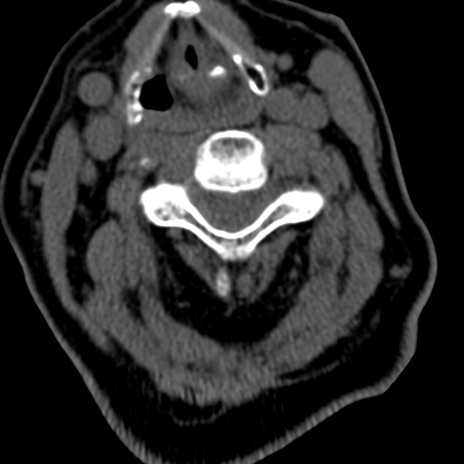

症例50 頚椎CT(横断像)

頚椎CT